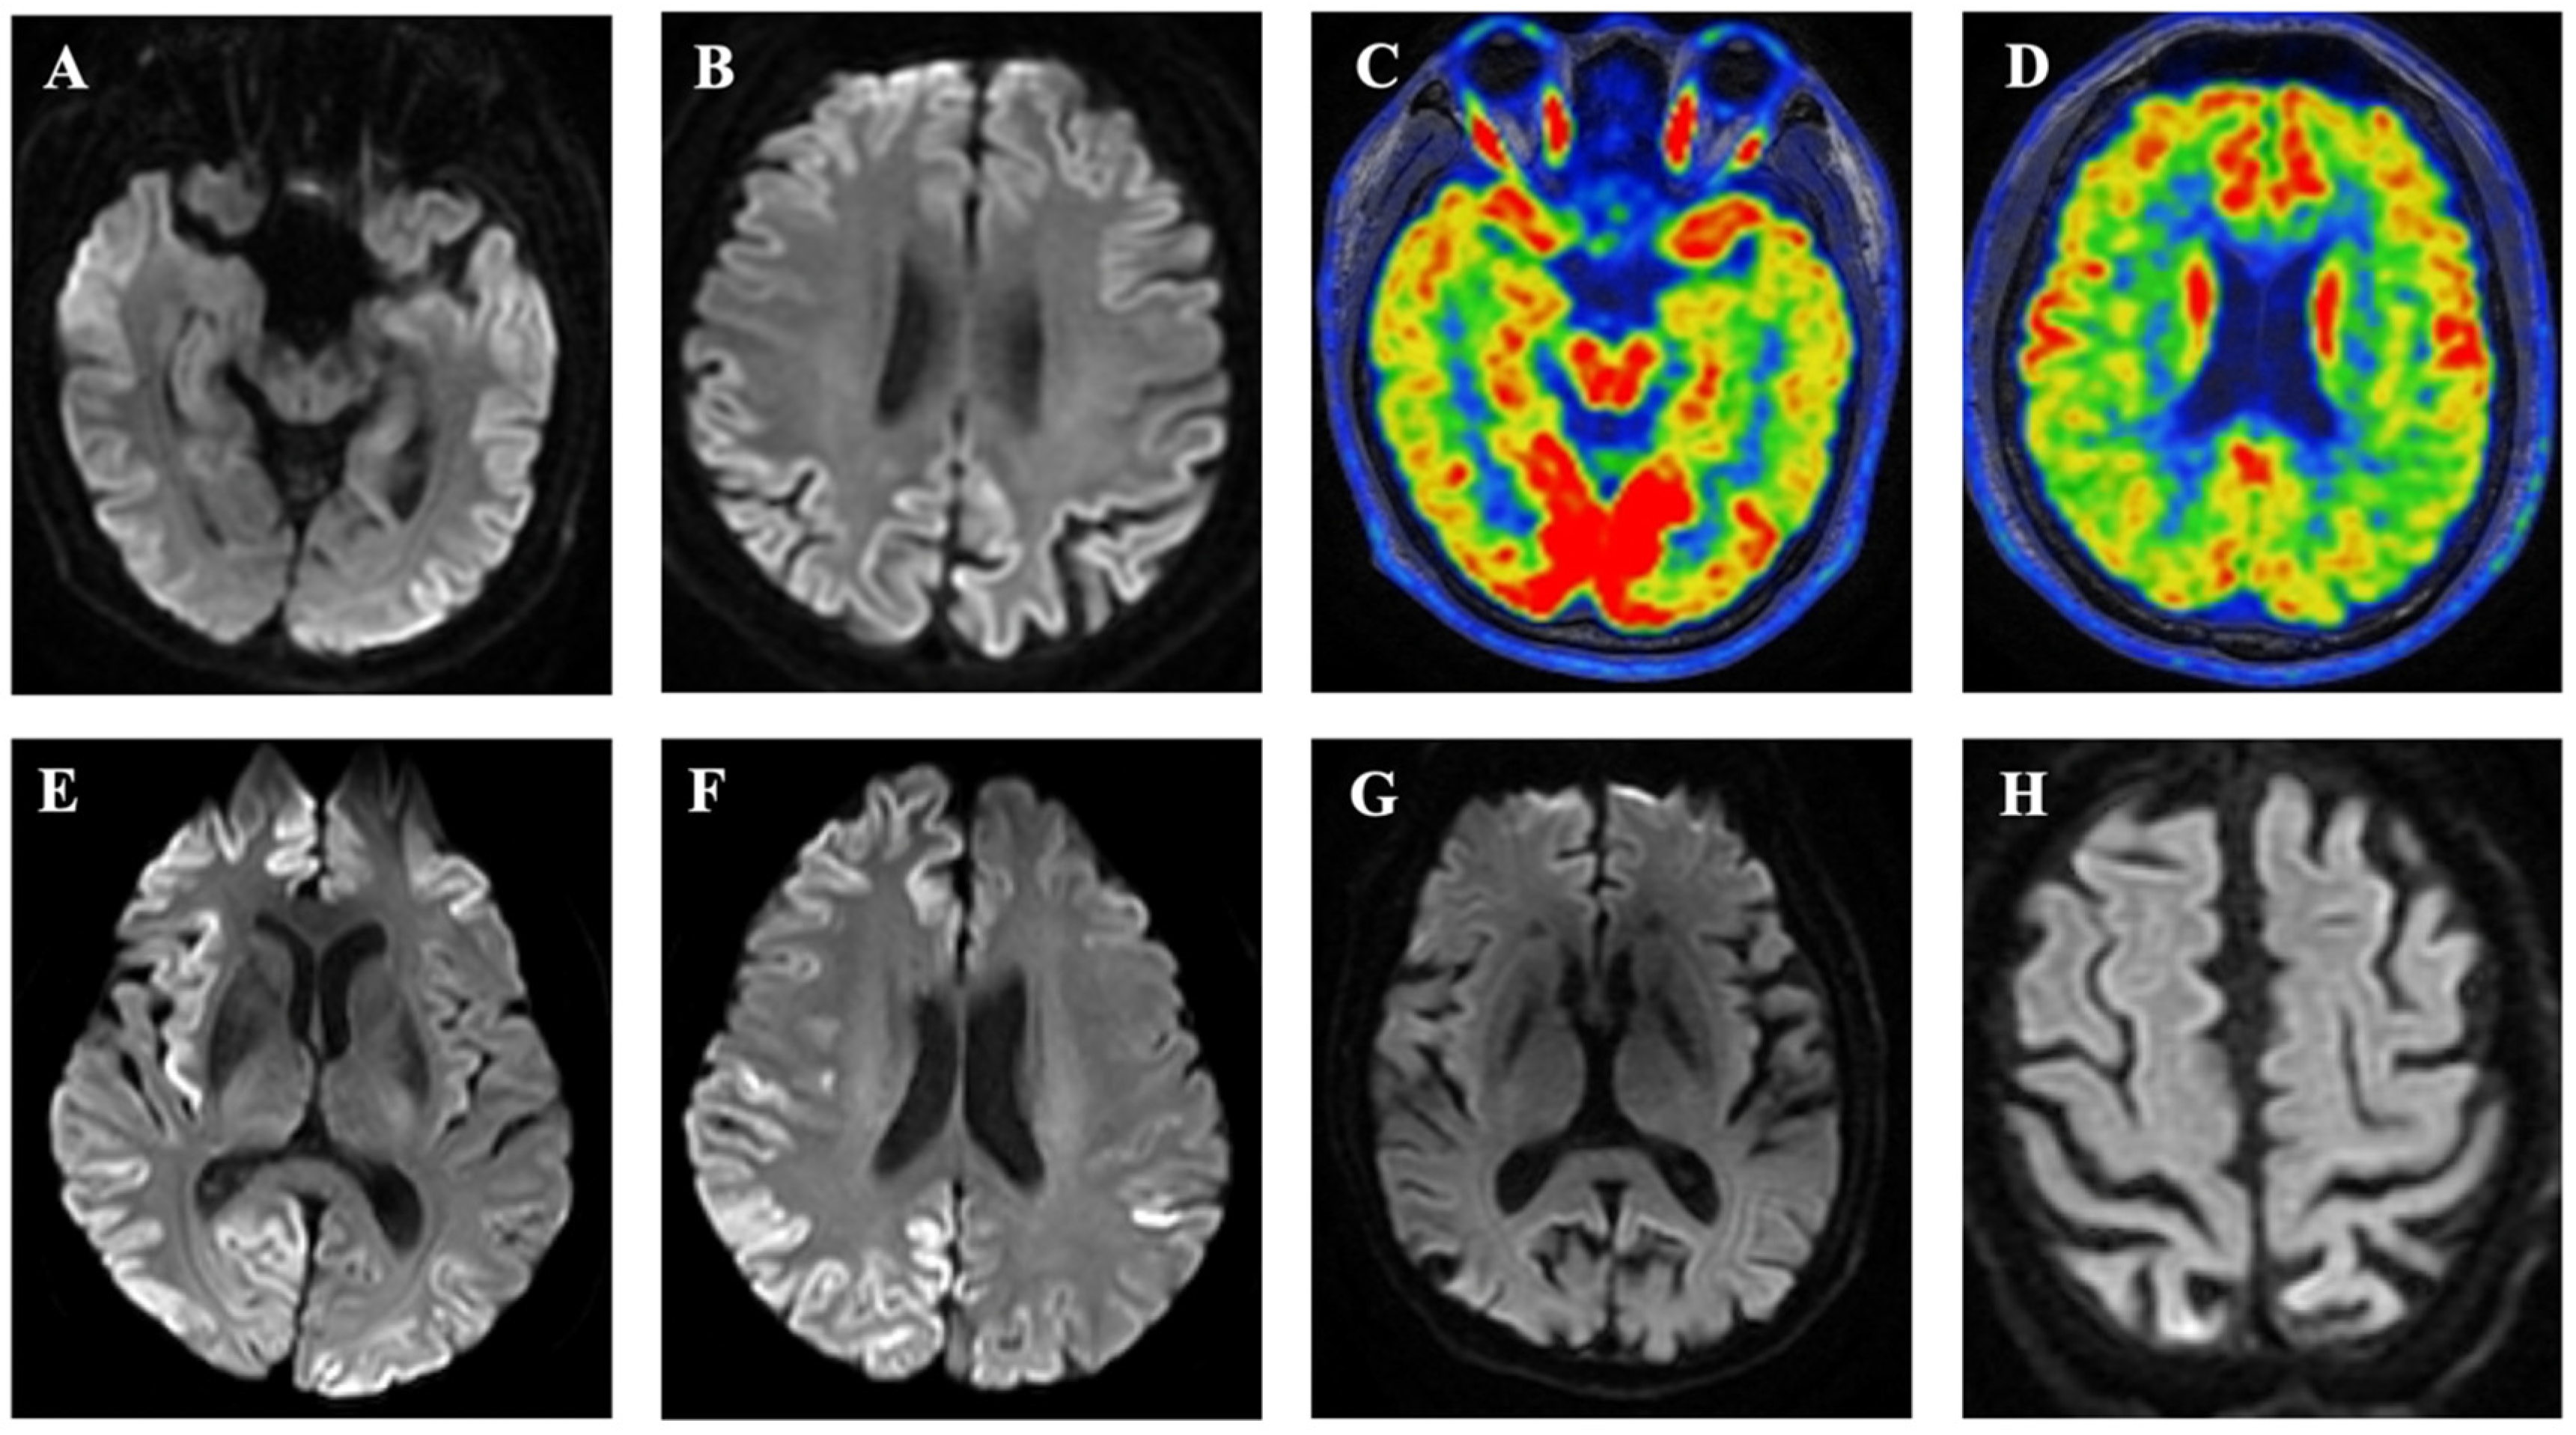

2.3.5. Magnetic Resonance Imaging

2.3.6. Positron Emission Tomography

| Hyperintensity on MRI, % | 3/7 (41.9) | 3/3 (100.0) | 0/4 | 0.029 |